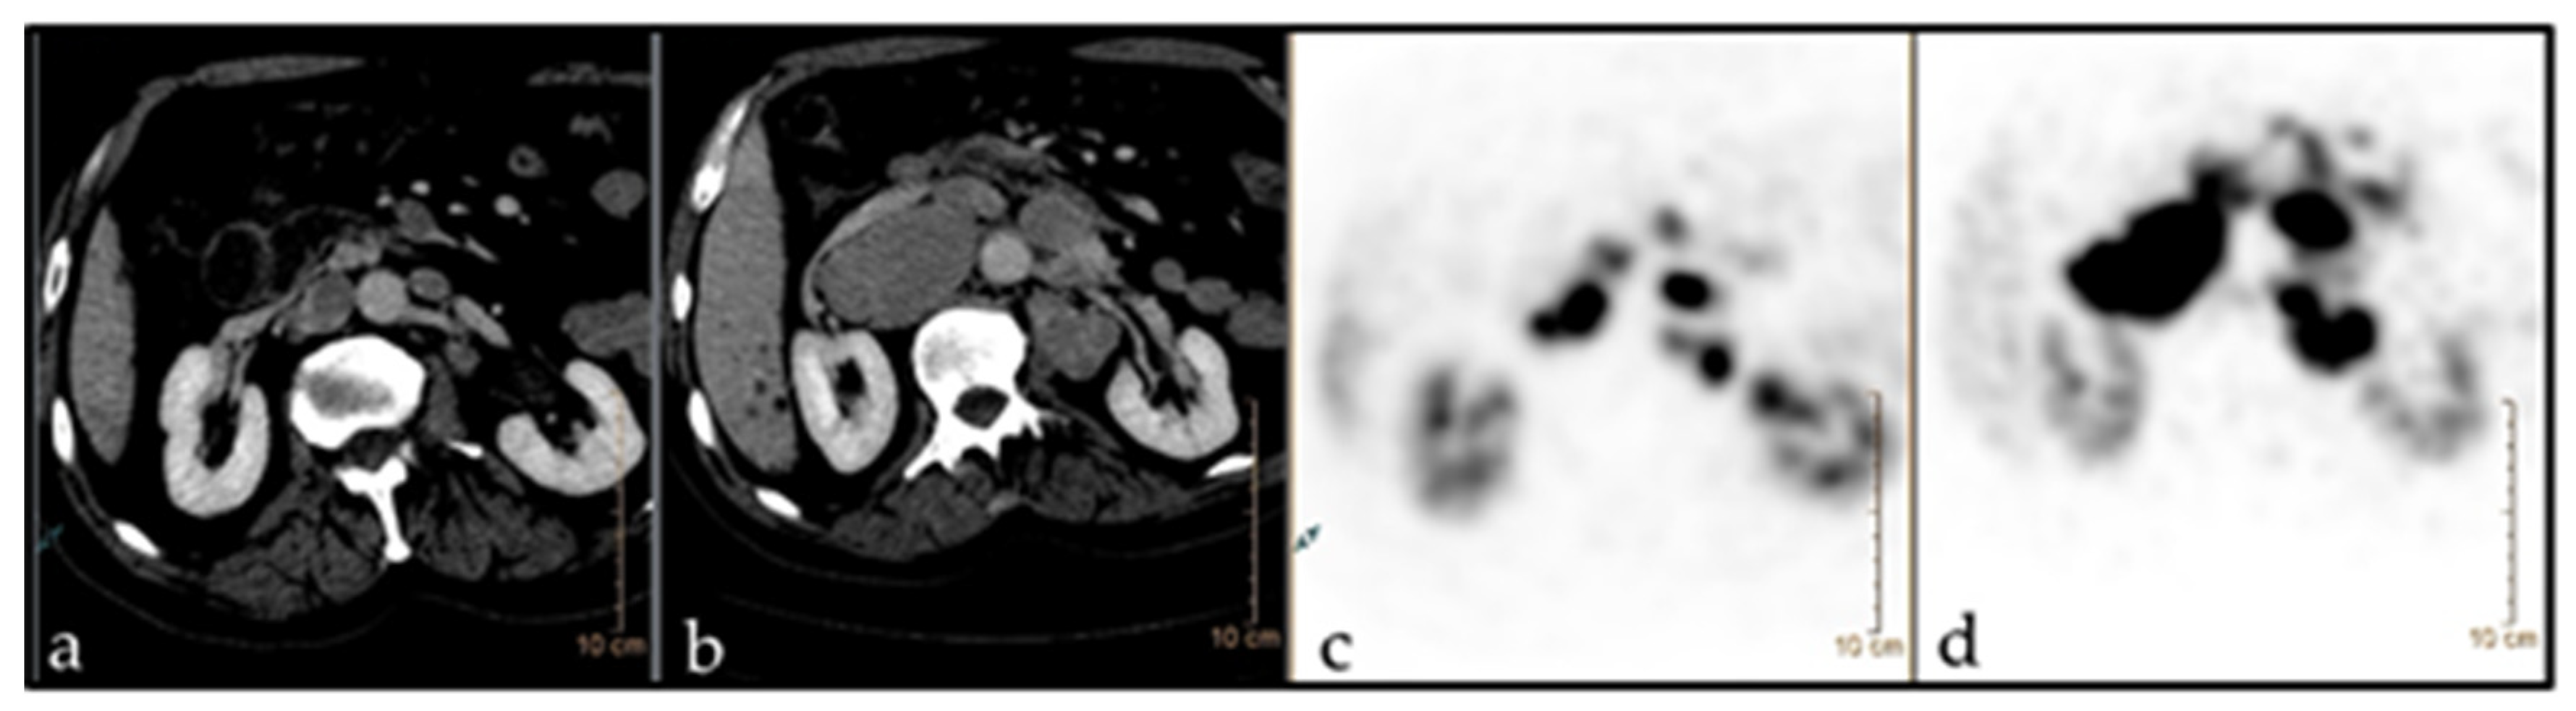

3.5. Pseudoprogression